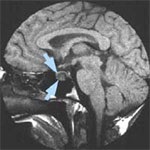

متخصص جراحی مغز و اعصاب